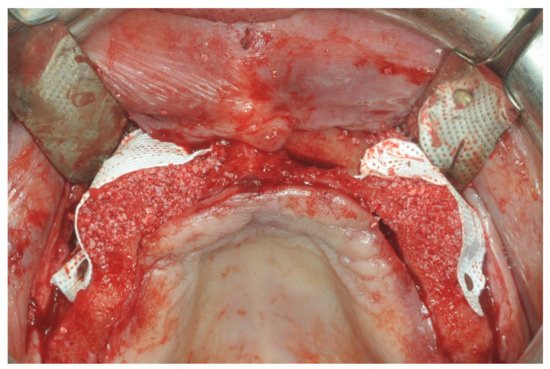

At this point, a non-resorbable high-density PTFE barrier (Cytoplast TXT-200, Osteogenics Biomedical, Lubbock, TX, USA) was designed on the basis of the bone defect shape and was distally blocked on the bone by two titanium pins (Kalos, Nike, Orbetello, Italy). A mixture of 50% autogenous bone harvested from the mandibular ramus with the use of a scraper and 50% inorganic bovine bone (Bio-Oss, Geistlich, Wolhusen, Switzerland) was placed in the recipient site and the membrane was pulled and blocked on the bone with two mesial pins. With this particular, and innovative, non-resorbable membrane management, the graft was compressed and fixed on the recipient bed (Figure 9, Figure 10 and Figure 11). The occlusal portion of the graft was then covered with a layer of a collagen resorbable barrier (Bio-Gide, Geistlich) (Figure 12) and peri-osteal incisions were performed to make the flap passive.

Figure 9. Occlusal view after implant placement.

Figure 10. Frontal view of the area to be augmented with the “sling technique”.

Figure 11. Particulate bone graft and non-resorbable membrane in position and far away from the incision line.